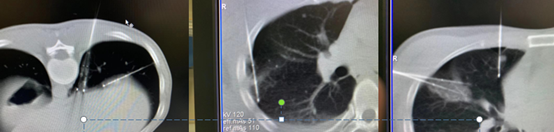

Selama pemeriksaan, saya menemukan bahwa pasien masih muda, memiliki fungsi paru-paru yang baik, dan tidak memiliki kontraindikasi lain, sehingga cryoablasi dapat dilakukan. Cryoablasi menyebabkan kerusakan minimal pada dinding dada dan mengurangi nyeri bagi pasien, sekaligus memungkinkan pembekuan dan penonaktifan tumor secara tepat menggunakan dua jarum krioablasi untuk memperbaiki lesi. Akhirnya, kami mengatasi tiga "bom waktu" bagi pasien dalam satu sesi ablasi.